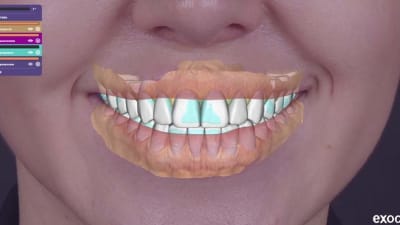

This article presents a clinical case of a comprehensive full-mouth rehabilitation in a 26-yearold female patient with an anterior open bite and accompanying mild chronic generalized periodontitis.